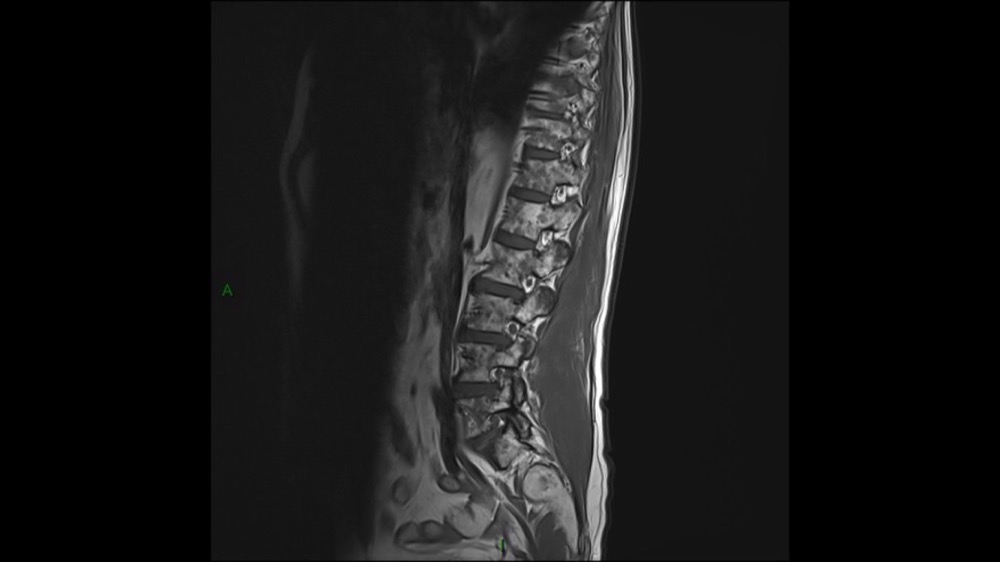

Lombo-cruralgie subaiguë trompeuse

Pascalie Jallerat 22/06/2020